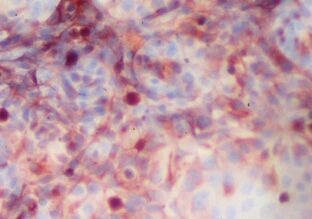

As tumors develop, they evolve genetically. How does the immune system act when faced with tumor cells? How does it exert pressure on the genetic diversity of cancer cells? Scientists from the Institut Pasteur and Inserm used in vivo video techniques and cell-specific staining to visualize the action of immune cells in response to the proliferation of cancer cells. The findings have been published in the journal Science Immunology...